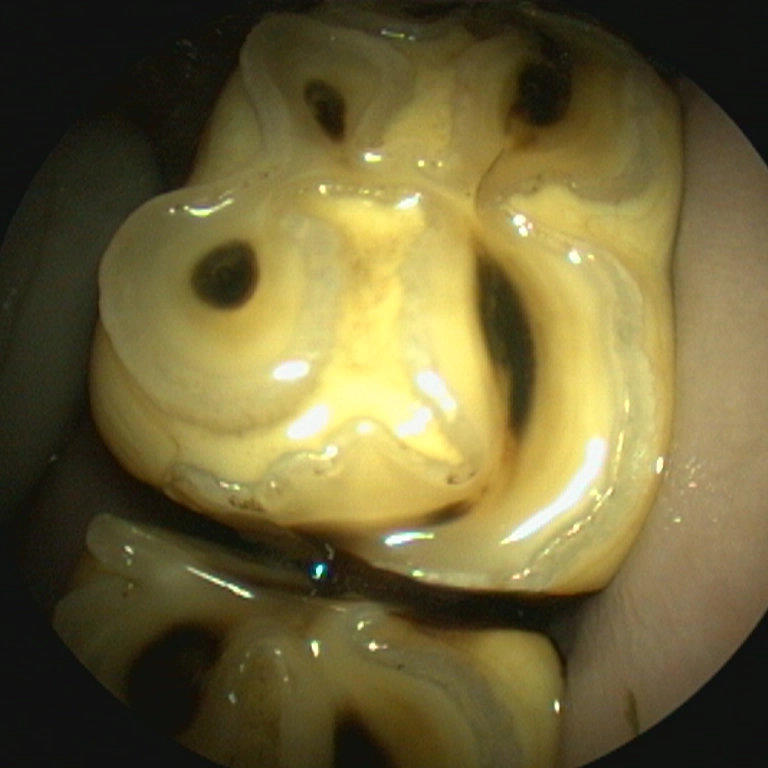

Diastema with feed impaction

Abnormal spaces between teeth allow feed material to become trapped and compressed into the gum tissue.

Over time, this leads to inflammation, infection, and damage to supporting structures if not addressed.